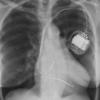

Ao nipple

(left superior intercostal vein)